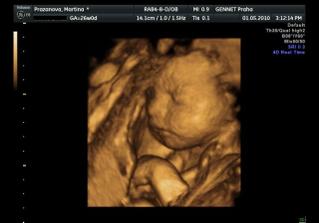

Určitě dám sem vědět i s aktuální fotečkou. Jména mám v pase. A 1.května jdeme na 4D UTZ, tak se moc těšíme 🙂

Letí to jak blázen, vždyť to znáš 🙂. Zatím nevíme nic, ale zítra jdeme na velký genetický UTZ, tak snad tam prcek nebude sedět v tureckém sedě jako minule 🙂))